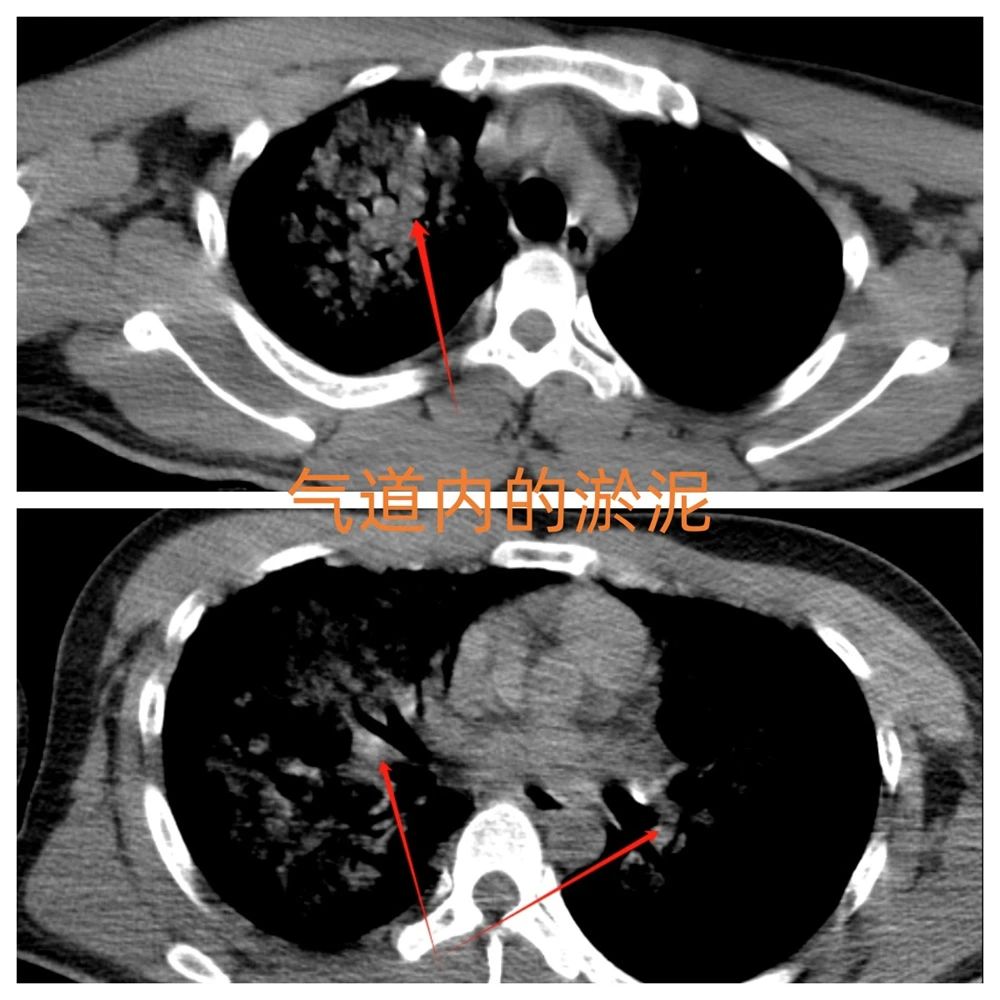

“气道内的淤泥不清除,所有治疗都是隔靴搔痒。”重症医学科主任黄智在查房时坚定地说道。团队迅速与呼吸与危重症医学科展开多学科联合会诊,一致认为唯有支气管镜下肺泡灌洗才能清除气道异物。随即科室护理团队及呼吸科气管镜室内的紧急消毒和科室病房的术前准备着。

在呼吸与危重症医学科主任吴德生的指导下,治疗团队在床旁为患者实施支气管镜检查。镜下画面触目惊心:气管及各级支气管内棕褐色淤泥团块,部分亚段支气管已阻塞。医护人员屏气凝神,通过生理盐水灌洗、负压吸引等精准操作,历经50分钟将气道内异物逐一清除。术后患者氧合指数逐步上升,呼吸机参数显著下调。